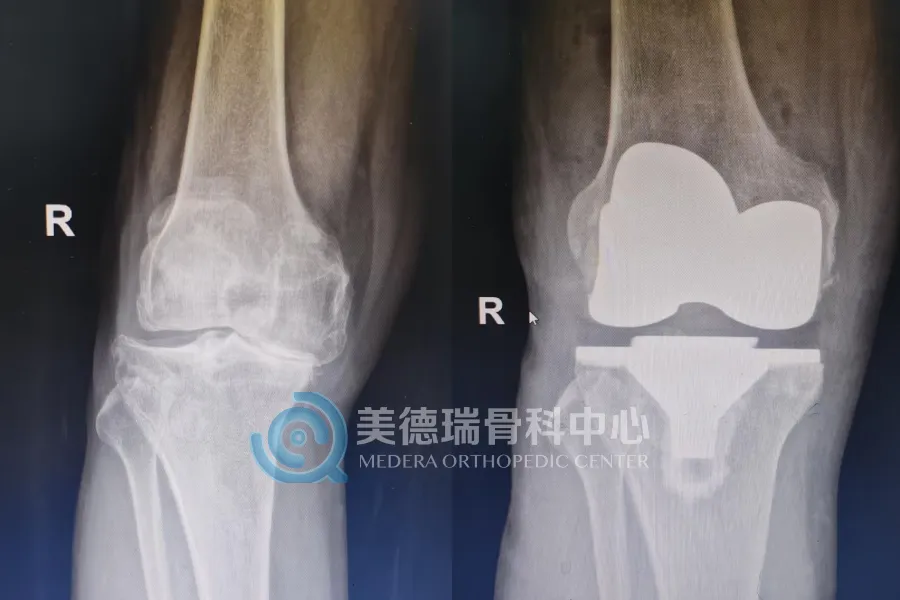

重度膝关节骨关节炎发展到后期,关节磨损明显,疼痛会反复加重,腿形和力线也会随之改变。到了这个阶段,全膝关节表面置换术是较为成熟、有效的治疗方式。手术的目标也很明确,就是减轻疼痛,纠正畸形,恢复负重和行走能力。

术前要把风险评估和基础病调控做细,术中要把截骨精度、软组织平衡和副损伤控制住,术后还要尽快把负重训练和康复衔接起来,这样患者才能更快恢复到日常生活状态。

近期接受治疗的一位68岁患者就是一个典型的例子。双膝疼痛已持续8年,近1个月明显加重,同时合并高血压和糖尿病。入院检查显示,其膝关节退变已较为严重,关节间隙明显变窄,力线也已发生改变,日常行走受到明显影响。经过术前评估和围手术期准备后,美德瑞骨科中心为其实施了全膝关节置换术。术后复查显示,患肢力线得到纠正;从术后站立和行走情况看,患者恢复平稳,已具备早期下地活动条件。